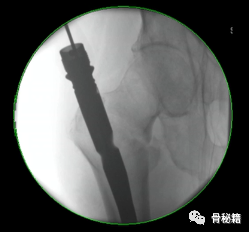

1、进钉点。髓内钉的位置在哪里最合适?

当然是髓腔的最中心,所以髓腔最中心的延长线就是最佳的进钉点。一般位于梨状窝。一个好的进针点可以保证力线,同时进钉后还有复位的作用,如果进钉点出现了偏移,可能整个手术都会有影响。好的开始象征着接下来手术的顺利,一定要取一个好的进针点。

他在正侧位的透视位置我们可以看到位于髓腔中心的延长线上

随着有外翻角的髓内钉的发明,我们现在目前用的可能多是大粗隆顶点进针的了

进针的角度,基本与股骨颈是垂直的角度